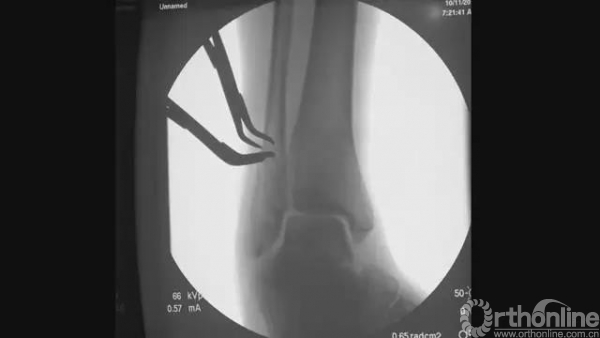

行远端锁钉

行下胫腓联合锁钉

拧入适合长度的锁钉